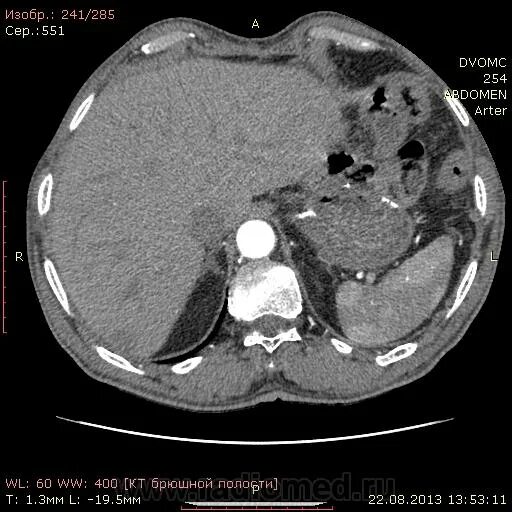

Могут ли метастазы перепутать